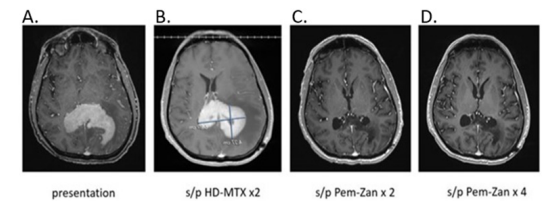

Figure 1:Brain MRI W/WO contrast of a 60-year-old male with PCNSL. Figure 1A was obtained at presentation; Figure 1B shows persistent PCNSL following 2 cycles of HD-MTX. The final two images reveal radiographic improvement after 2 (Figure 1C) and 4 (Figure 1D) cycles of Pem-Zan, respectively.

The patient received an initial cycle of HD-MTX 3.5g/m2 with a brief steroid taper with improvement in neurological symptoms. A brain CT scan wo contrast, 12 days post first dose of HD-MTX, demonstrated improvement in mass effect and a 3.1 cm right parietal lesion with surrounding edema consistent with treatment response. The patient then received a second dose of HD-MTX 3.5 g/m2 with a brief dexamethasone taper, which was completed approximately 1 week after HD-MTX administration . However, before the scheduled third dose of MTX, the patient presented with recurrent significant worsening neurologic deficits, including the inability to ambulate. A brain MRI w/wo contrast demonstrated progression of the right parietal lobe mass, now measuring 6.5 x 5.0 x 4.2 cm with confluent periventricular and corpus callosum enhancement of the splenium and body, as well as left parietal lobe involvement (Figure 1). Surrounding T2/FLAIR hyperintensity was observed, which was suggestive of edema and infiltrating tumor. A 7 mm midline shift to the left was noted, but there was no evidence of hydrocephalus. In comparison to prior non-contrast CT scans, the mass effect of the CNS lymphoma was significantly more prominent, with invasion into the posterior horns of both lateral ventricles, causing a midline shift and increased surrounding vasogenic edema. Despite the initial radiological and clinical response to HD-MTX, the patient's disease progressed after two cycles. The patient was started on dexamethasone 4 mg orally 4 times a day with incomplete improvement of neurological symptoms.

The patient was enrolled in a clinical trial of pemetrexed-zanubrutinib (Pem-Zan) (NCT05681195). At that time, the patient had been on 16 mg dexamethasone per day for over 9 days. A CT scan with contrast of neck, chest, abdomen, and pelvis, testicular Doppler US, and a full spinal MRI w/wo contrast found no new systemic involvement, and stable small size lymphadenopathy consistent with a history of CLL. No evidence of lymphoma was found on ophthalmologic examination. The patient was then treated with pemetrexed 900 mg/m2 intravenously every 3 weeks for a total of 5 cycles and zanubrutinib 160 orally twice per day. Per the protocol, zanubrutinib was held two days before, on the day of, and on the day after pemetrexed to avoid drug to drug interaction (DDI). The rationale for this measure is based on report by Lionakis et al. 2017 indicating that there may be an antagonistic relationship between BTK inhibitors and anti-folate agents [21]. Supportive care consisted of peg-filgrastim with each cycle, folic acid and B12 supplementation, and dexamethasone the day before, the day of, and the day after pemetrexed (Pemetrexed Package Insert). Following two cycles of Pem-Zan, an MRI of the brain w/wo contrast revealed near complete resolution of extensive areas of confluent periventricular enhancement and corpus callosum enhancement, with minimal residual corpus callosum splenium linear enhancement and reduction in vasogenic edema and mass effect (Figure 1). This was consistent with a partial response (PR) in accordance with the International PCNSL Collaborative Group's (IPCG) criteria [22]. Dexamethasone was gradually tapered and discontinued completely on the day 9 of cycle 3 of Pem-Zan.

Upon the completion of cycle 4 of Pem-Zan, an MRI of the brain wo contrast revealed continued treatment response as indicated by complete resolution of enhancement in the treated tumor area, reduced residual FLAIR signal, and some cystic changes consistent with unconfirmed CR (CRu) [22] (Figure 1). The patient reported feeling well overall and had intact cognitive function (mini-mental state examination, MME 29/30). The patient completed a total of 5 cycles of Pem-Zan treatment without significant complications, with resolution of neurologic symptoms. The patient experienced transient grade 1 thrombocytopenia, which resolved spontaneously, as well as transient grade 1 elevation in liver function tests, which resolved with dietary changes. There were no grade 2 or higher adverse events reported. The patient remained an outpatient throughout Pem-Zan treatment. Before ASCT, positron emission tomography (PET) CT showed no metabolically active/high-grade lymphoma (Deauville score of 1). Bone marrow biopsy demonstrated 1% involvement by CLL and was negative for LBCL. The patient underwent carmustine-thiotepa 20 mg/kg (BCNU-TT 20) conditioning, ASCT, and experienced neutrophil engraftment on day +9. They were discharged home on day +13, remaining transfusion-free [23].